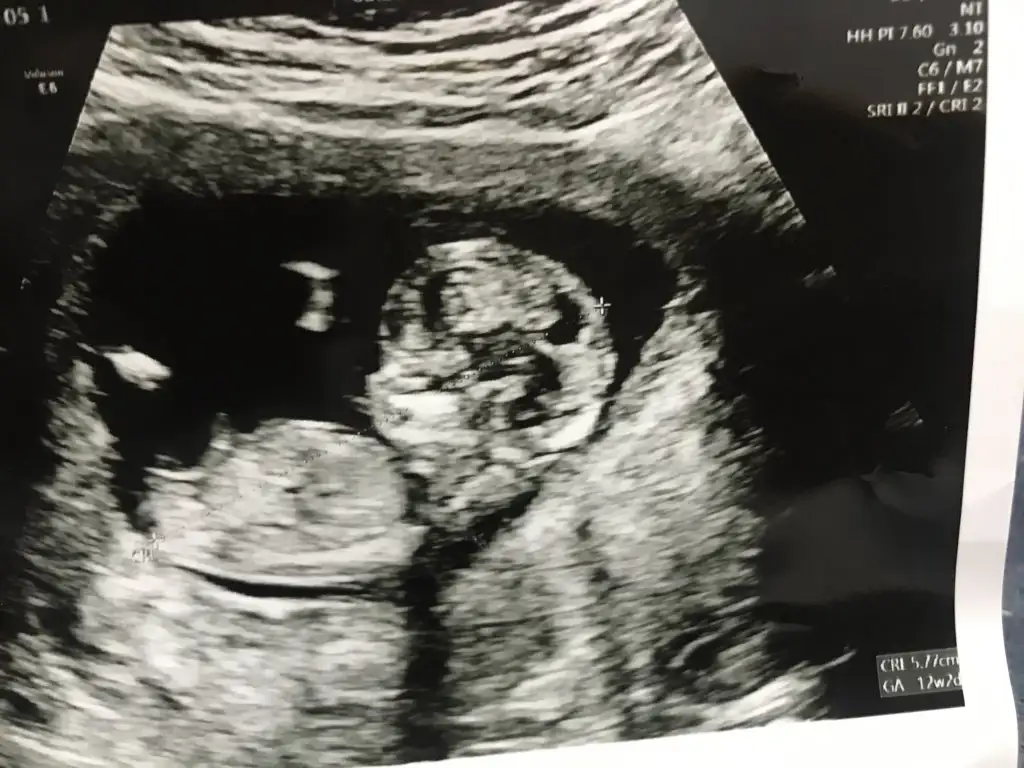

Bana da bakabilir misiniz 12+2

Eklentiler

• 03C91A9F-DC60-42B4-83D6-B415BB44D01A.webp

42,9 KB · Görüntüleme: 139